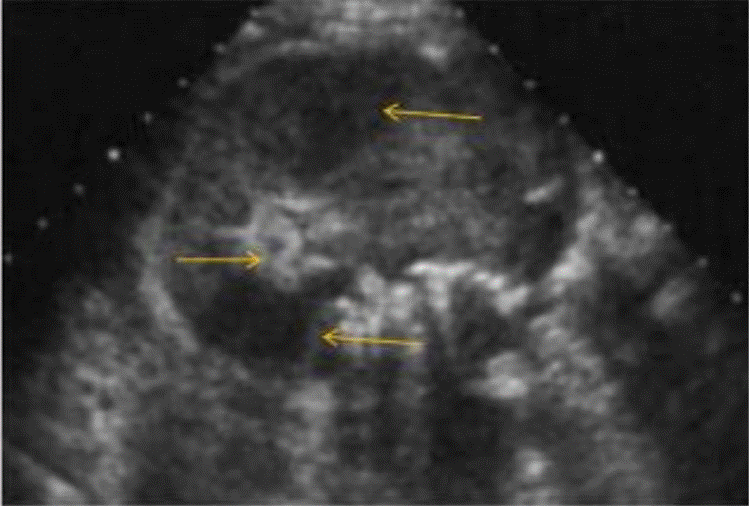

La ecografía abdominal total mostró hallazgos sugestivos de PNE izquierda (Figura 1), por lo que se solicitó valoración por urología; este servicio indicó continuar con la misma terapia antibiótica y realizar UROTAC que mostró microlitiasis renal bilateral, litiasis ureteral izquierda y proceso infeccioso inflamatorio con presencia de gas en el riñón izquierdo, lo que indicó diagnóstico de PNE izquierda tipo 2 (Figuras 2 y 3). Ante los hallazgos radiológicos y el reporte de urocultivo positivo para Escherichia coli multisensible, se decidió hacer rotación de cubrimiento antibiótico a carbapenémicos debido al alto riesgo de mortalidad.

Fuente: documento obtenido durante la realización del estudio

Figura 1 Ecografía renal y de vías urinarias en la que se evidencia riñón izquierdo agradado con focos hiperecogénicos en su interior y ecos de gran amplitud sugestivos de gas.